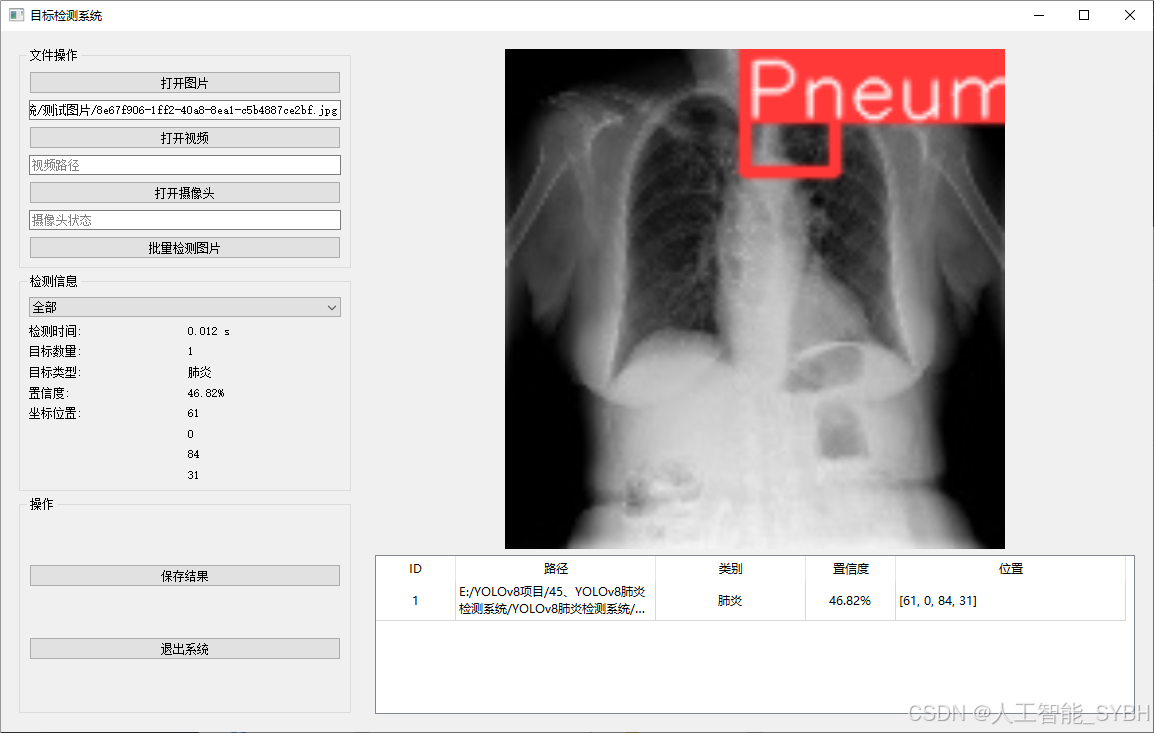

二、项目功能展示

系统功能

✅ 图片检测:可对单张图片进行检测,返回检测框及类别信息。

图片检测

该功能允许用户通过单张图片进行目标检测。输入一张图片后,YOLO模型会实时分析图像,识别出其中的目标,并在图像中框出检测到的目标,输出带有目标框的图像。批量图片检测